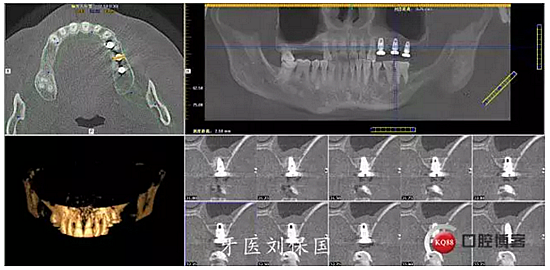

4.六個月后二期CT: